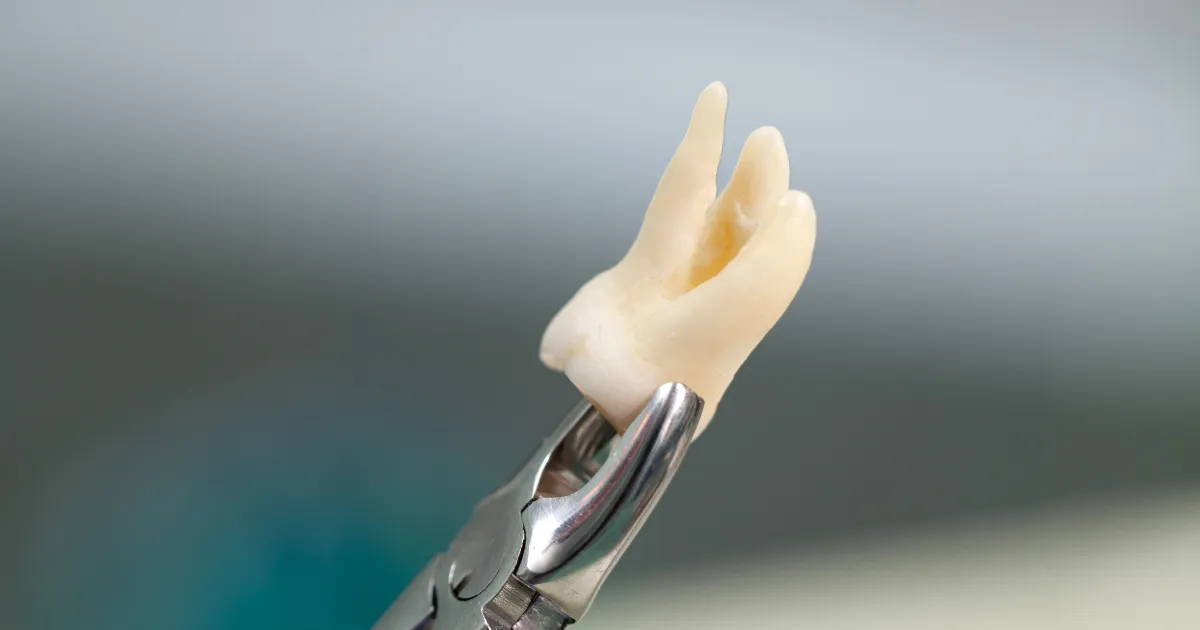

智齿的拔除,尤其是当智齿深埋在牙床或接近神经时,往往是一项高难度的手术。对于那些对牙科手术有极度恐惧或特殊需求的患者来说,全身麻醉有时是必要的选择。然而,在歯科ハミール高田88(高田马场牙科),我们并不建议所有患者选择全身麻醉,除非是特殊情况,例如患有严重的牙科恐惧症或需要特殊照护的患者。通常情况下,我们的经验丰富的专家可以通过局部麻醉进行复杂的智齿拔除,避免将患者转诊至大学医院进行全身麻醉。本文将详细介绍全身麻醉下智齿拔除的优点、风险,以及歯科ハミール高田88的处理方式。

全身麻醉下拔除智齿的三大好处

全身麻醉在智齿拔除中的优势主要体现在以下三个方面: